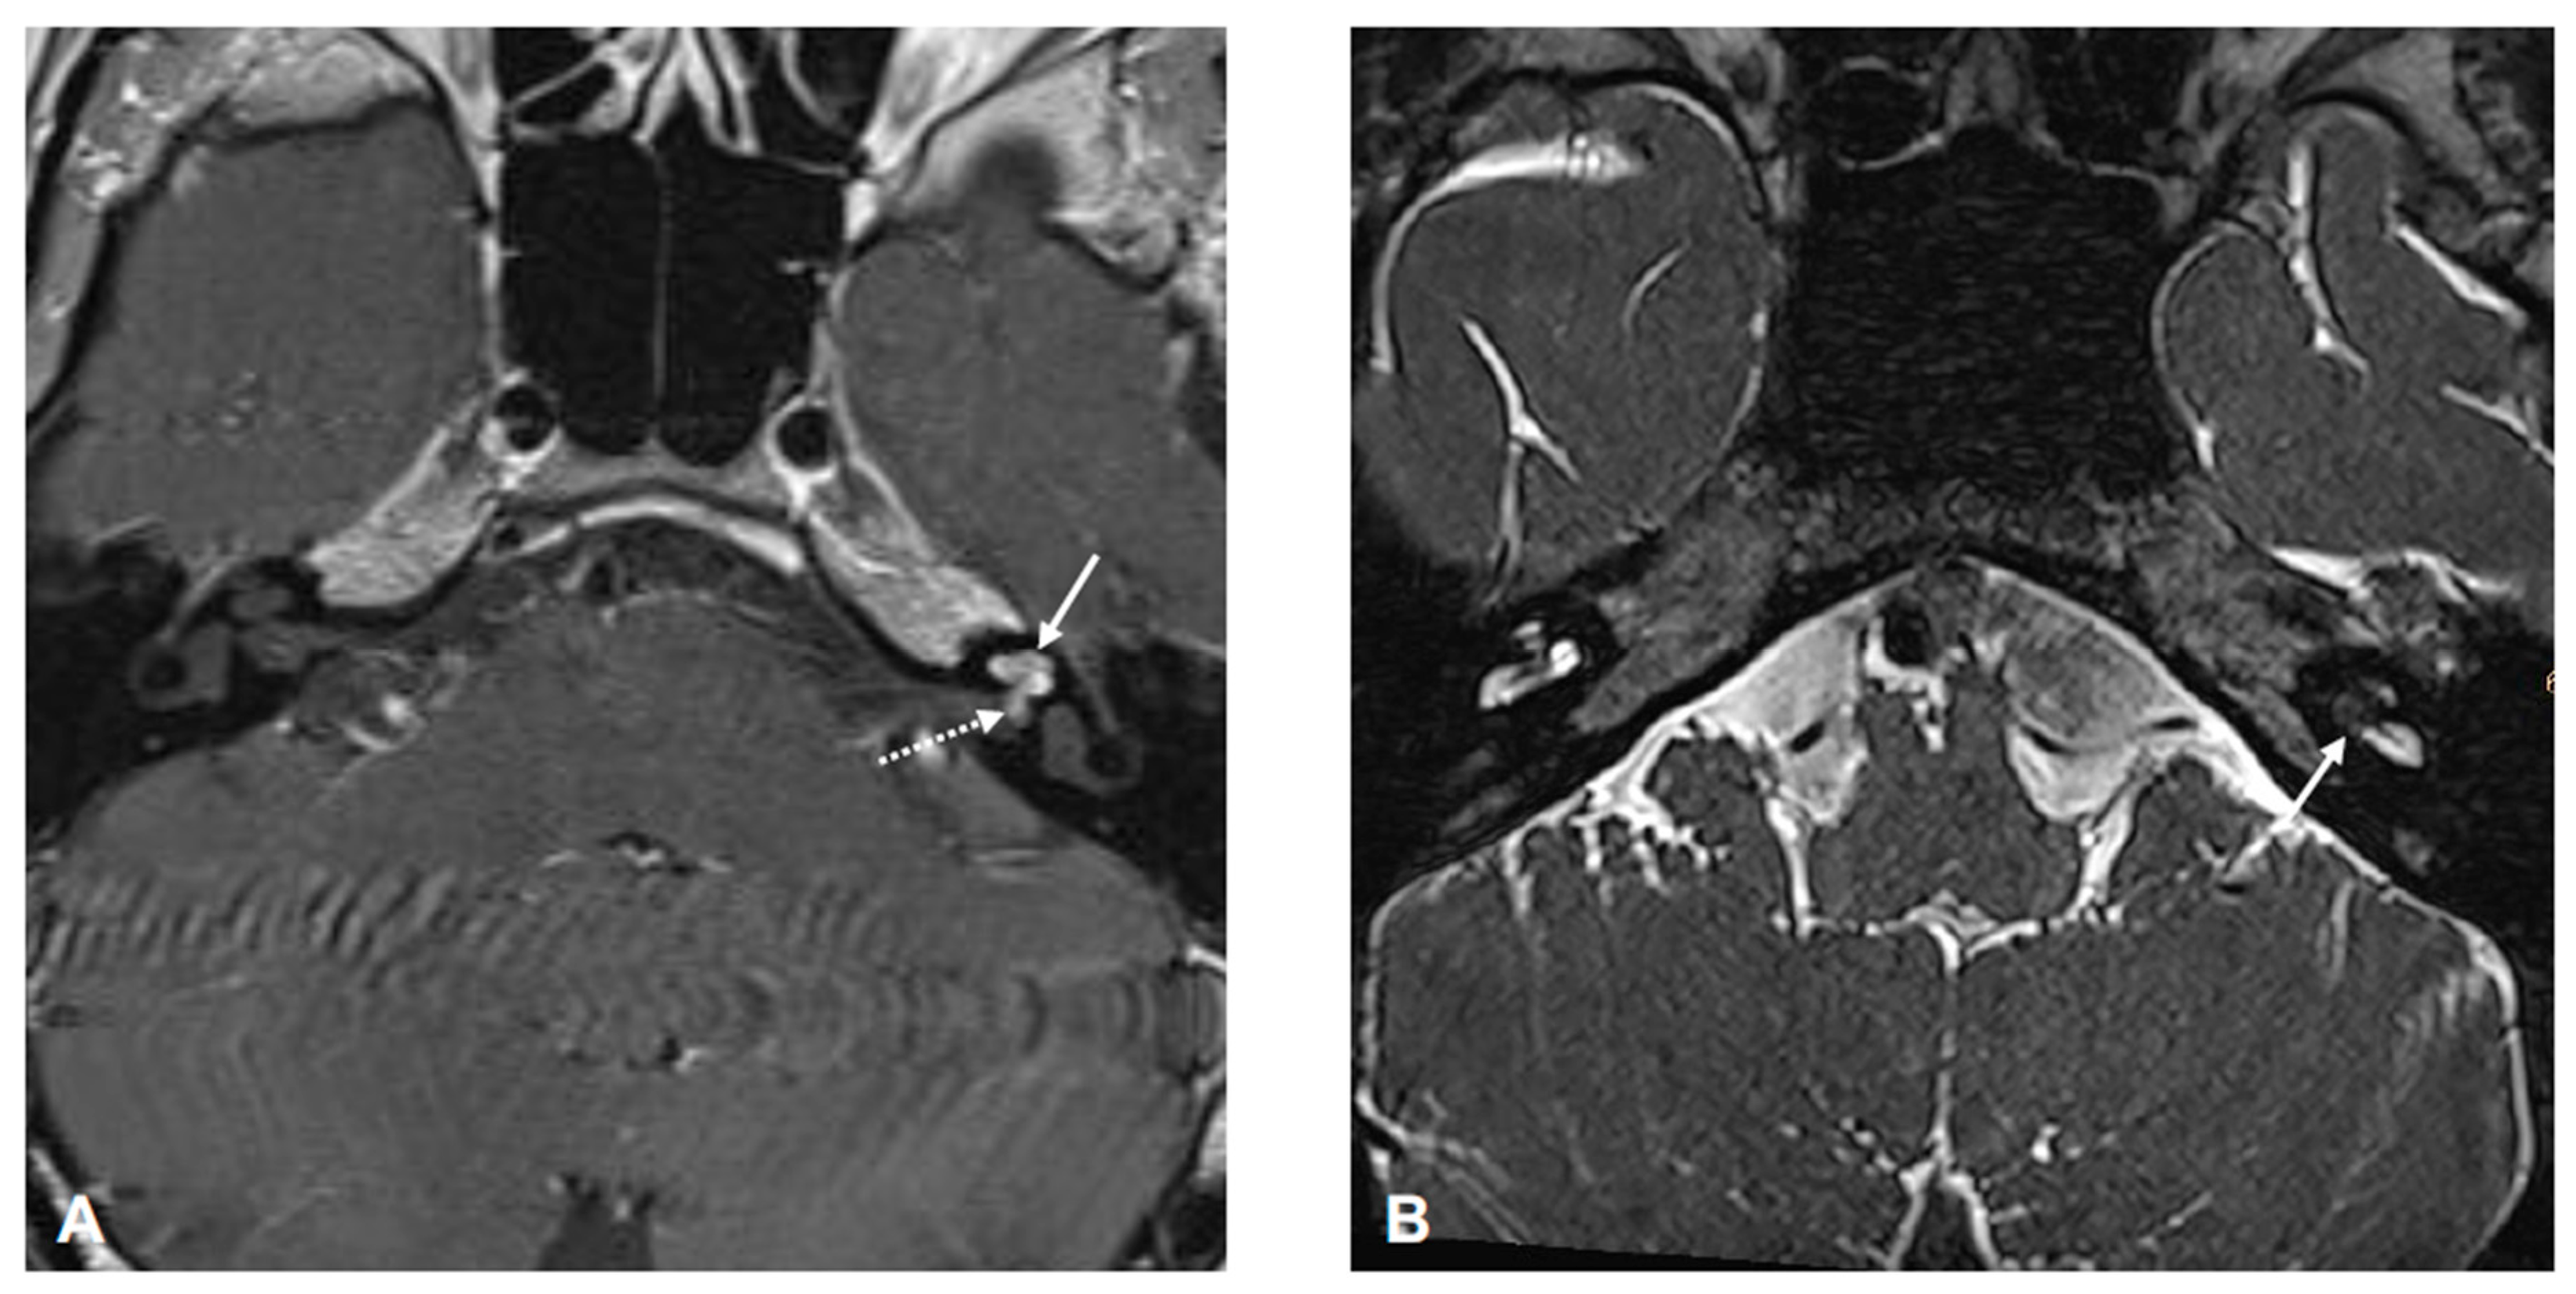

2. Patient Information and Clinical Findings

3. Diagnostic Assessment and Interpretation